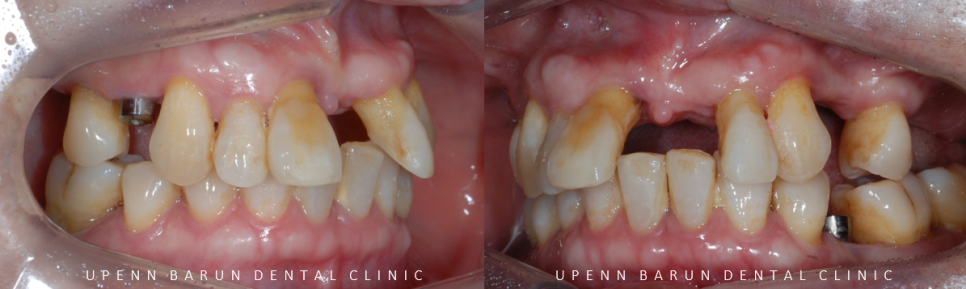

임플란트 2개 식립 후 구내사진

먼저 오른쪽 위, 왼쪽 아래에 총2개의 임플란트를

식립하셨습니다 ^^

1년뒤인 23년 7월

잘 고정된 임플란트의 본을 뜨고, 최종 보철물이 완성된 사진입니다.

교합이 무너져 있었던 이전과 달리

맞물리는 치아가 생기며 환자분께서

식사를 잘 하실 수 있게 되셨어요 ㅎㅎ

(오른쪽 아래 치아의 경우 상악 임플란트가 적응되는대로 곧이어 치료를 진행하시기로 하셨습니다^^)

총 치료기간 1년4개월 (22/3/28~23/7/17)

상악에 총 7개 임플란트를 통해

총 12개의 치아를 만들어 드렸는데요~!

임플란트를 효율적이고 정확한 위치에 심게 되면

치아의 갯수대로 전체 임플란트를 하지 않아도

임플란트끼리 연결하여 인공치아를 만들어 사용하실 수 있습니다.